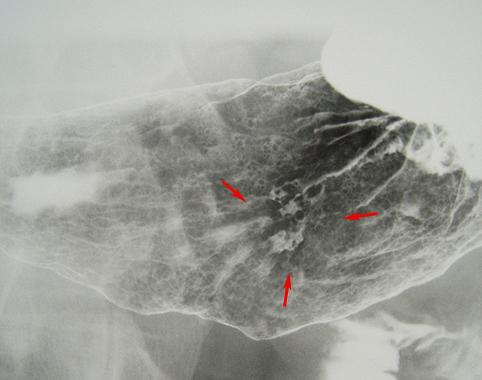

Criteria of Hist.ClassificationMalignant epithelial tumor/Signet-ring cellcarcinoma

LocationStomach/Angle

Technique, MethodX-ray

Macroscopic TypesType 0/IIc (IIc+III) Superficial depressed and excavated type

Size20 - 24

Depth of Tumor Invasionmucosa